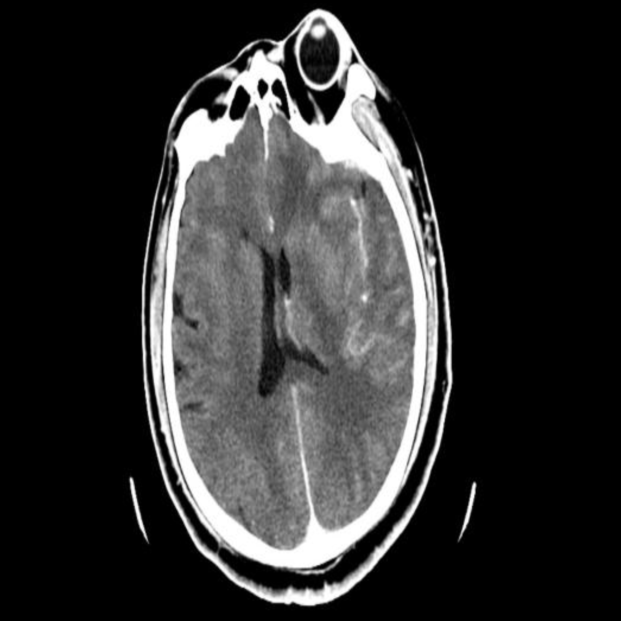

急诊头部CT:左侧脑组织密度减低,水肿,脑沟、脑回变浅、脑室受压,左侧大脑中动脉高密度征。

术后即刻

术后3h

术后1天

术后3天CT

术后6天CT

术后11天CT

本例患者术前ASPECT评分较低,经取栓治疗后,血管通畅良好,术后即刻复查颅脑CT无出血,但术后3h内脑组织水肿明显,合并高灌注水肿、脑疝表现,及时给予去骨瓣减压手术,挽救患者生命,挽救缺血半暗带的脑组织,保留脑功能。所以,对于取栓术后病人的围术期管理非常重要,直接决定患者的预后。本例患者通过对术前的预判、术后对意识、瞳孔的密切观察,及时采取有效的去骨瓣减压外科干预措施,得以安全度过脑水肿期,最后通过神经功能康复,期待患者有良好的预后。